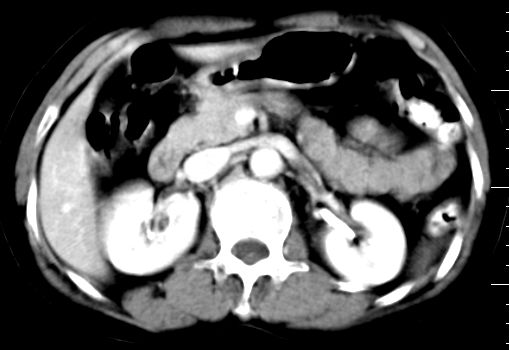

标题: CT10752:F,52岁,反复上腹部疼痛,平扫+增强. [打印本页]

f、52岁,反复上腹部疼痛2年。肺结核病史10多年,胸片双上肺结核纤维化。

ct表现:

肝大小形态未见异常,肝内外胆管无扩张,肝s8段见一动脉期明显血管样强化结节,门脉期呈高密度,延迟期呈等密度,胆囊不大,增强扫描见胆囊及胆囊颈管壁增厚,有强化。

双肾灌注良好,代谢增快,动脉期肾盂见造影剂,左肾下极背侧见一略低密度病灶,延迟期见似不强化囊肿,双侧肾上腺未见异常。

胰腺及脾未见异常。肾门水平腹膜后见小淋巴结。腹腔未见积液征象。

诊断:

1、胆囊炎(轻度)。

2、肝s8段结节,考虑小血管瘤。

3、左肾下极低密度灶,考虑囊肿可能性大,建议随访,除外小肾癌(无强化可以基本除外)。

4、目前ct表现尚不能解释患者上腹部疼痛,建议上消造影检查,除外胃炎等疾患。